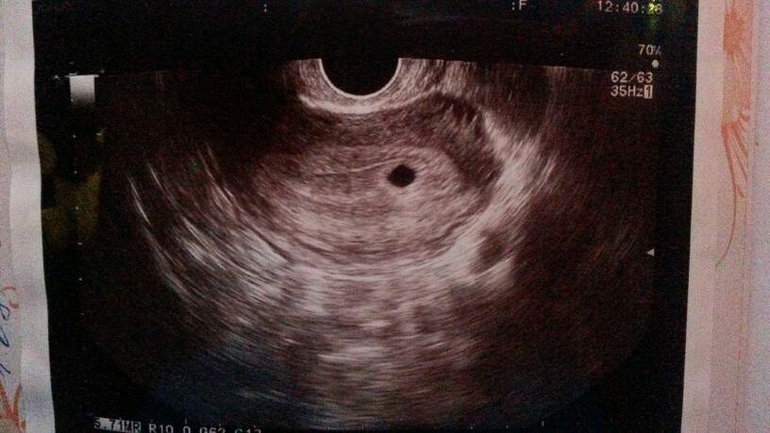

5 неделек и 3 дня)

Неа, доктор не фотал, да и я без телефона на кресле была, рот разинула)) у меня в ПЯ было видно мааааленькую козявочку)))

На первом скрининге когда была, там тоже не фотали, я попросила чтобы на паузу нажали и с монитора на телефон щелкнула быстренько ) А на этом УЗИ там тоже козявка была)Просто как то не удачно сфоткала она) Ктр там был сколько то мм)Не помню уже скок

Наша динамика))) Медленно, но ярчаем!!! Результаты в 7 недель и 1 день